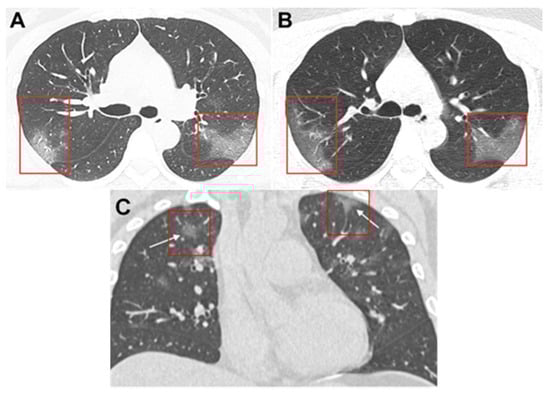

- Lei, J.; Li, J.; Li, X.; Qi, X. CT Imaging of the 2019 Novel Coronavirus (2019-nCoV) Pneumonia. Radiology 2020, 295, 200236. [Google Scholar] [CrossRef][Green Version]

- Chung, M.; Bernheim, A.; Mei, X.; Zhang, N.; Huang, M.; Zeng, X.; Cui, J.; Xu, W.; Yang, Y.; Fayad, A.Z.; et al. CT Imaging Features of 2019 Novel Coronavirus (2019-nCoV). Radiology 2020, 295, 200230. [Google Scholar] [CrossRef][Green Version]